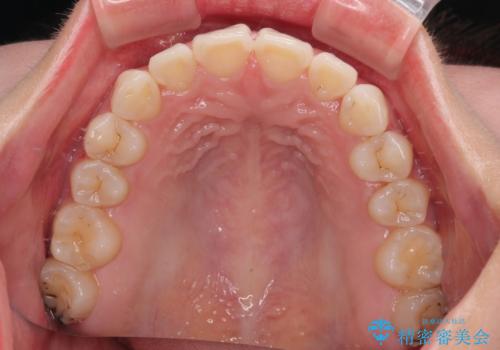

- 前歯のデコボコと突出感を気にして来院された患者様です。

極力目立たない装置を希望とのことで、インビザラインを用いて非抜歯で矯正治療を行うこととしました。

事前に親知らず2本を抜歯し、多少歯列を後方に移動できるように準備をした上で、なるべく歯と歯の間を削ることなくデコボコを解消できるように計画しました。

前歯の捻れを改善するとともに、口元が少しでも引っ込むように治療計画を立て、仕上げることができました。